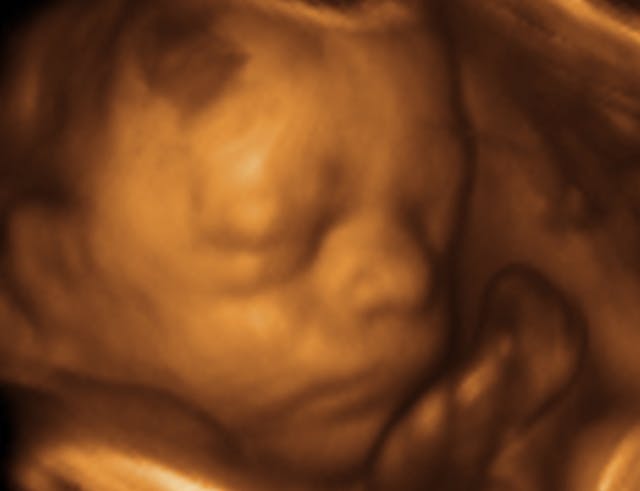

Seeing her child on the ultrasound screen, and gaining a better understanding of the growing life she was carrying during her initial visit, Hillary had been even more impressed with the genuine compassion the staff showed to her at the appointment.

Looking back, Hillary recognizes how much of a difference it made to see her child on screen.

“Many of our clients don’t realize the tiny miracle of life growing inside of them until they see the baby’s picture on an ultrasound,” Carol Dodds, executive director of A Woman’s Friend, said. “Once they see the heartbeat, they know without a doubt that this is not a blob of tissue, but rather a little human being relying on them for sustenance and protection, that the decision they make will save or end a life.”